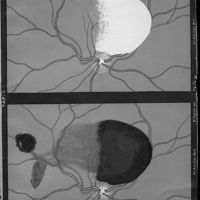

Ophthalmoskopische Studien

- Ophthalmoskopische Studien

- Mitteilungen aus kliniken und medicinischen Instituten der Schweiz, Vol. 3, pp. 545-82

- Siegrist - Hutchinson (syndrome de)